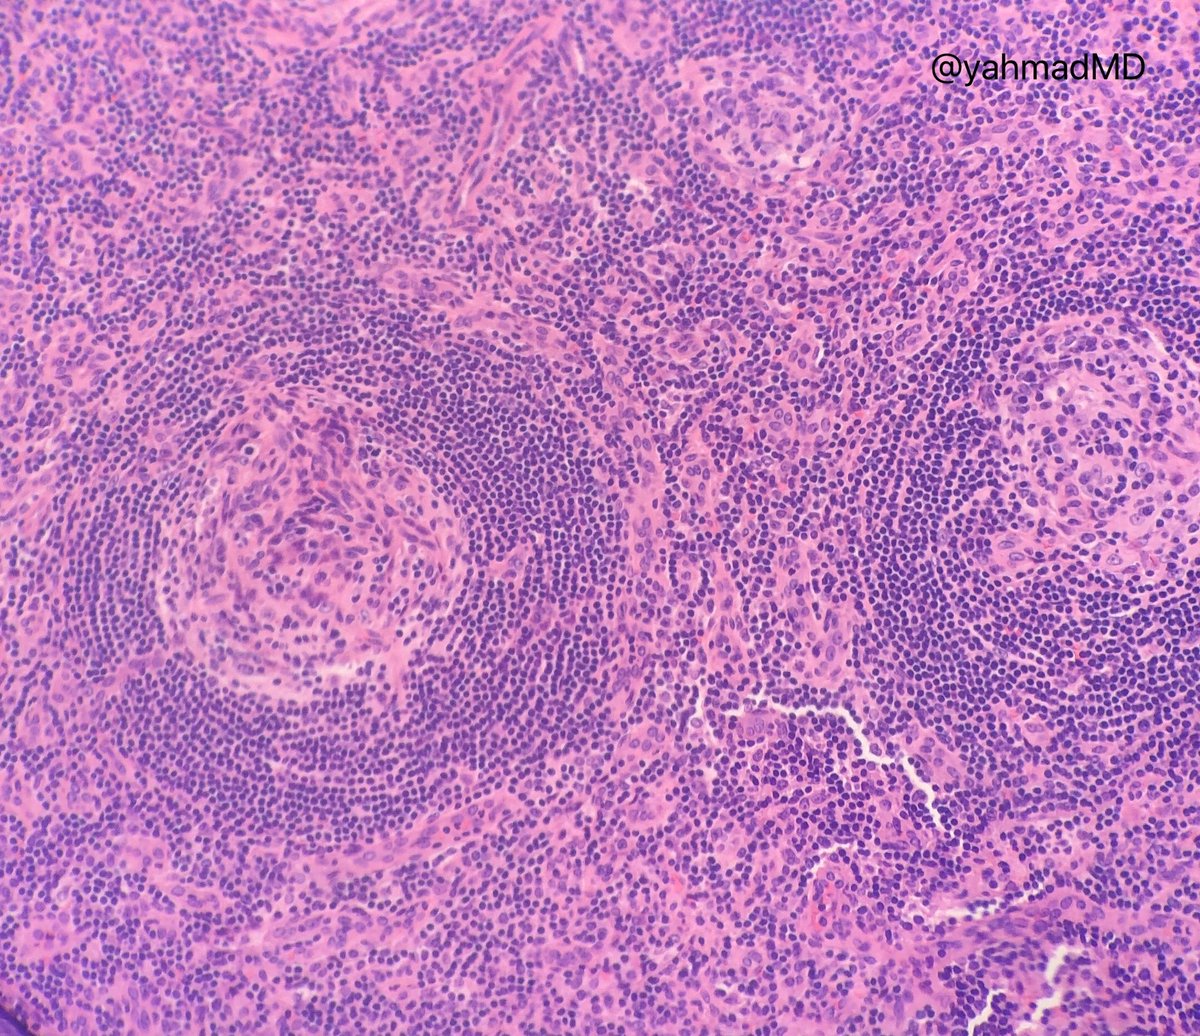

Beautiful example of hyaline-vascular type Castleman disease! - Lollipop sign (arrows: tangentially cut vessels radially penetrating germinal centers)

- Onion skinning of mantle zone lymphocytes

So many food analogies in pathology! #Pathology#Hemepath#MedTwitter#MedEdpic.twitter.com/A3UZBabI3O